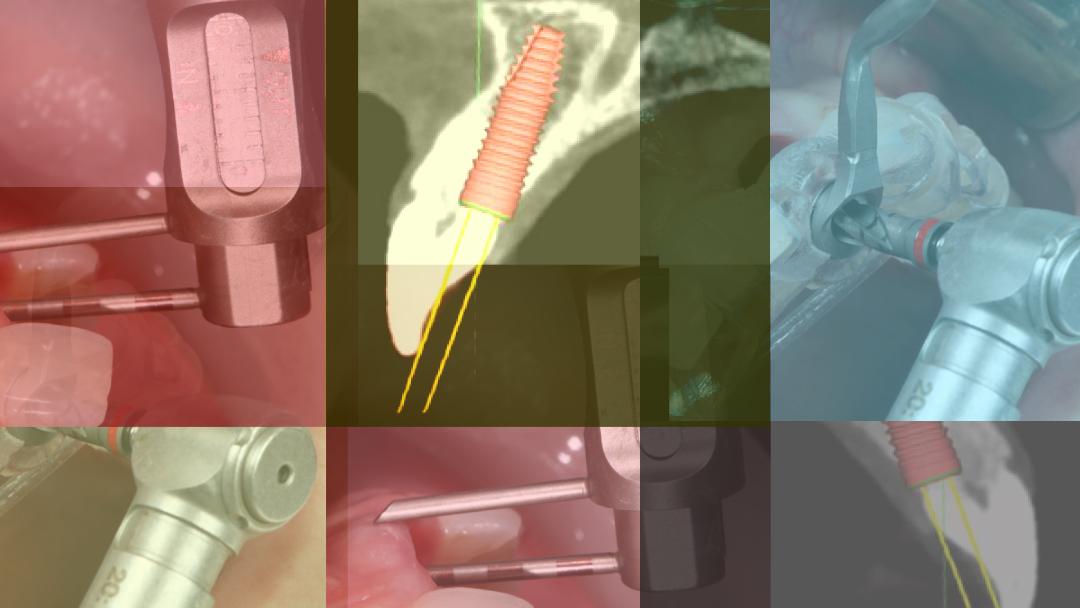

Ψηφιακή Εμφυτευματολογία (Μέρος 1 – ΧΕΙΡΟΥΡΓΙΚΗ) Ασφάλεια & Προβλεψιμότητα στην Εμφυτευματολογία

Conduct date:

21-22/04/2018 09-10/06/2018